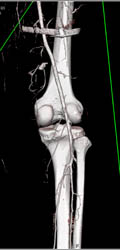

Osteosarcoma Iliac Bone